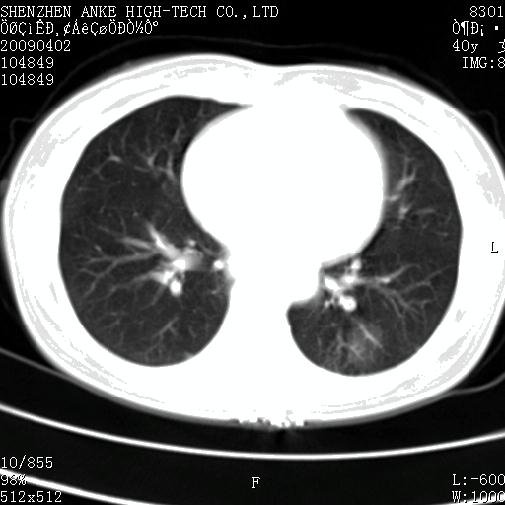

以下是引用随光逐影在2009-4-2 12:16:00的发言:[br]考虑左肺下叶背段继发性肺结核,结核球形成;建议追踪复查。

以下是引用gudu医生在2009-4-2 11:27:00的发言:[br]周围型肺癌

以下是引用卜一在2009-4-2 13:31:00的发言:[br][br] [br] 空洞壁厚不均 胸膜凹陷征。周围型肺癌可能 不排除干酪坏死型肺结核及坏死性肉芽肿。 [br] [br]支持!

以下是引用ct诊断高手在2009-4-2 13:04:00的发言:[br]空洞壁厚不均 胸膜凹陷征。周围型肺癌可能 不排除干酪坏死型肺结核及坏死性肉芽肿。